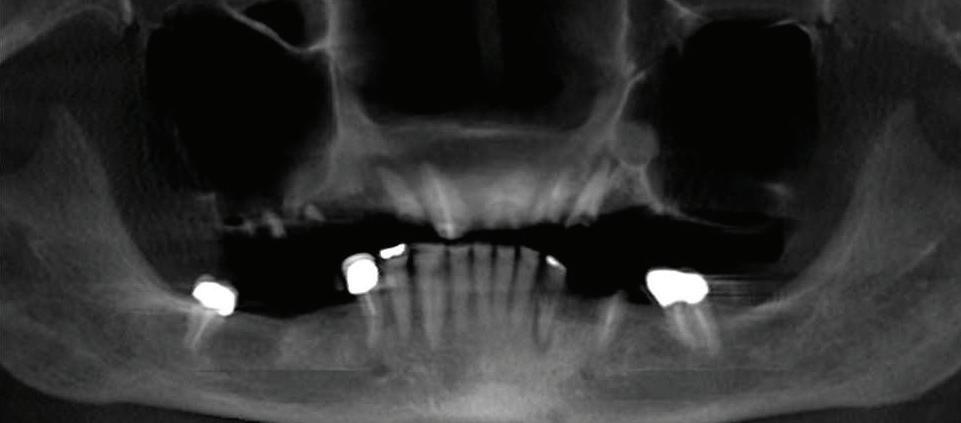

Can just four implants replace all of the teeth on the top or the bottom of your mouth? Thanks to advances in dental implant technology, that answer is a resounding yes.

Believe it or not, tooth loss is extremely common among adults, especially as we age. In fact, more than 35 million people in America are missing all of their upper and/or lower teeth. Rather than living with the discomfort and hassles of dentures, many people are opting for what is called “all-onfour” dental implant restoration.

Here’s where it gets really interesting: You do not need a dental implant for each and every one of your missing teeth. All you need is four precisely placed implants on the top of your mouth, and four on the bottom, to restore your full smile. That’s the beauty of the all-on-four. And because the implant is made of titanium, it has the unique ability to fuse to living bone and function as part of it. So eventually, the dental implant becomes part of the jawbone and serves as a strong, long-lasting foundation for your new teeth.

this bone fusion has another important benefit: it prevents future bone loss in the jaw. This helps to maintain a more youthful facial structure – and better oral health. But perhaps the biggest surprise about the all-on-four is how quickly it can transform your life.

At your All-On-Four consultation, you’ll receive a 3D CT Scan. This scan will help determine if you need implants and assist your doctors in creating your treatment plan. So if you want to learn more about dental implants, simply schedule a consultation with an All-On-Four provider. It’s the best way to find out how dental implants can change your life.

All-on-Four: One Full Arch Of Teeth, Four Dental Implants

To fully understand this remarkable technique for replacing teeth, you should first understand what a dental implant is. An implant is a small titanium screw that fits inside your jawbone and replaces the root-part of a missing tooth. Minor surgery is required to insert the implants. Once the implant is in place, a crown is attached to give you a highly realistic-looking and functional prosthetic tooth.

Besides ensuring that your implants are permanently fixed in place, this bone fusion has another important benefit: it prevents future bone loss in the jaw. This helps to maintain a more youthful facial structure – and better oral health. But perhaps the biggest surprise about the all-on-four is how quickly it can transform your life.

Next, they will begin the implantation process. This means they will insert the titanium screws into your jawbone. Most likely, they will place two implants toward the front of your mouth and two towards the back of your mouth so the “anchors” can evenly bare the force of the denture.